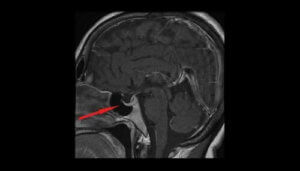

De mest relevante tests, som hjælper med at bekræfte diagnosen, er af synsfeltet, CT-scanning og MR-scanning af hjernen.